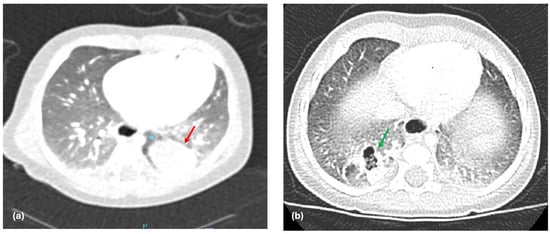

One of the main findings of our study is the significant difference in venous drainage between ILS and ELS, which offers substantial evidence for the importance of venous drainage patterns in predicting the type of BPS. Our results show that 96% of ILS cases drain into the pulmonary vein (Figure 1a), whereas 83% of ELS cases have systemic venous drainage (Figure 1b). This observation supports the hypothesis proposed by Stocker et al. in 1986 [12]. Interestingly, it is important to note that a small percentage of patients did not conform to the expected drainage patterns, for instance, 4% of ILS patients exhibited systemic venous drainage, while 17% of ELS patients demonstrated pulmonary venous drainage. These outliers underscore the complexity of BPS and suggest that venous drainage alone may not provide a definitive classification in all cases.

Figure 1. (a) CT scan showing a right lower ILS draining in to right inferior pulmonary vein (red arrow: pulmonary venous drainage); (b) CT scan showing a left lower ELS draining into the left adrenal vein (green arrow: systemic venous drainage).